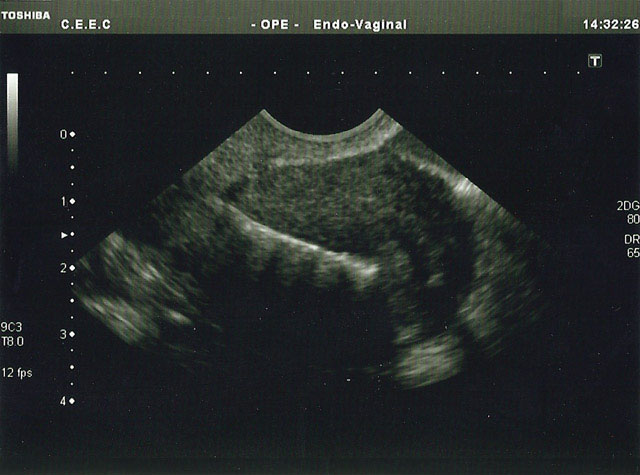

inicialexames a clinicapreçáriogaleriaFAQcontactos